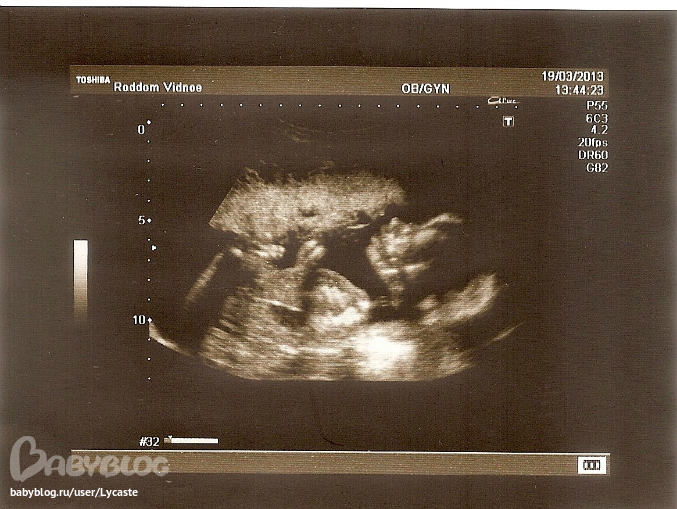

В понедельник ходила к гине, официально в декрете, выдали обменную карту. Вчера ходила на УЗИ. Масяня развивается хорошо.

Сегодня пошла 32-я неделька)))